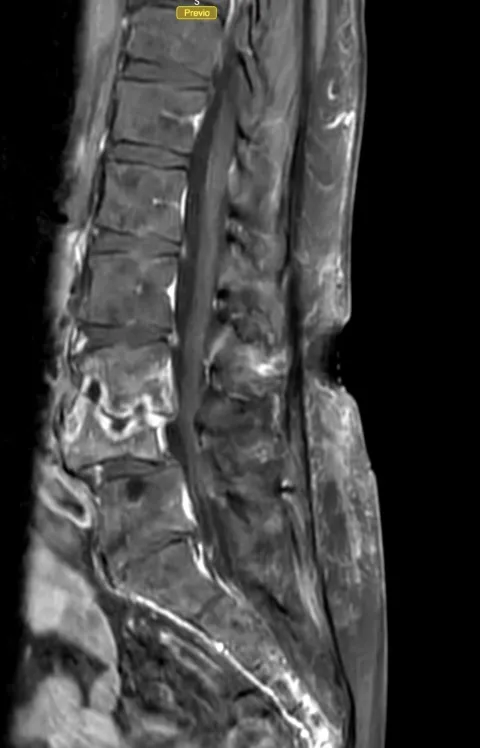

Resonancia magnética (RM)

Constituye la prueba de imagen de elección para el diagnóstico y seguimiento de la espondilodiscitis. La RM presenta una sensibilidad y especificidad superior al 90%, permitiendo una visualización óptima del disco, los cuerpos vertebrales, los abscesos epidurales y la afectación de partes blandas paravertebrales.

La clasificación de la espondilodiscitis por resonancia magnética distingue diferentes estadios según los hallazgos radiológicos:

El seguimiento de los pacientes con espondilodiscitis se basa fundamentalmente en dos pilares:

- PCR y VSG seriadas: la normalización progresiva de estos marcadores indica una buena respuesta al tratamiento.

- Resonancia magnética de control: permite evaluar la resolución de la infección, la presencia de abscesos residuales y el grado de fusión vertebral.